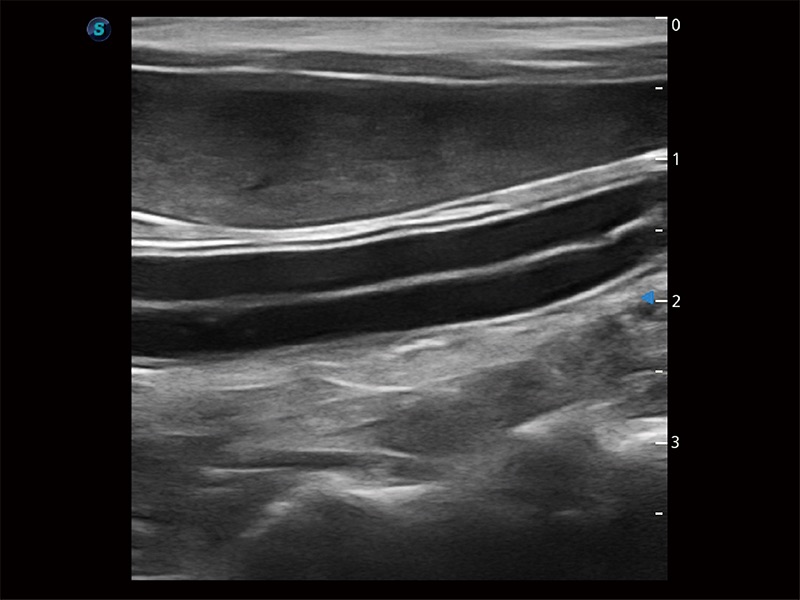

為精細結(jié)構(gòu)及組織邊緣提供高清晰度的圖像和更大的成像視野。幫助減輕醫(yī)生的用眼疲勞,快速精準獲得測量的數(shù)據(jù)。

ProPet 80 全新的動物超聲智能軟件和豐富的探頭群,為動物醫(yī)生提供了高清晰度和精細分辨率的圖像,無論在寵物、馬科、畜牧還是實驗室動物等應用中都可以輕松應對,為您的日常工作帶來滿意的體驗。